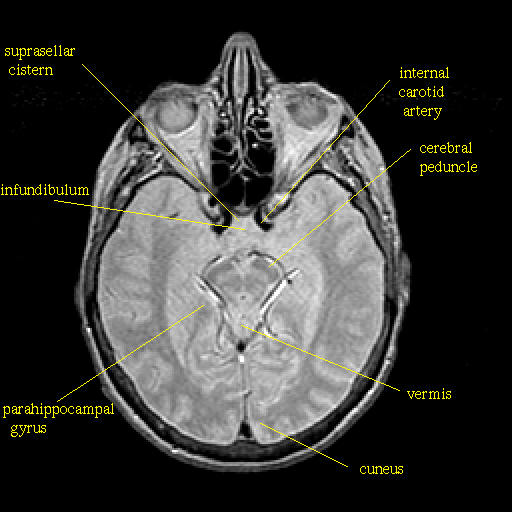

Proton density-weighted structural MR: Slice 22

Slice 22